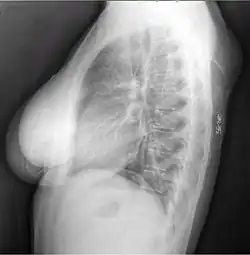

A physical exam is typically the easiest way to diagnose it. Rarely, a tissue biopsy or imaging may be required. The imaging modality of choice is magnetic resonance imaging (MRI) because it has superior sensitivity of distinguishing it from liposarcoma as well as mapping the surrounding anatomy.[22]

X-ray showing lipoma -

Bone formation may be seen in both lipomas[26] and liposarcomas (a well-differentiated one pictured).